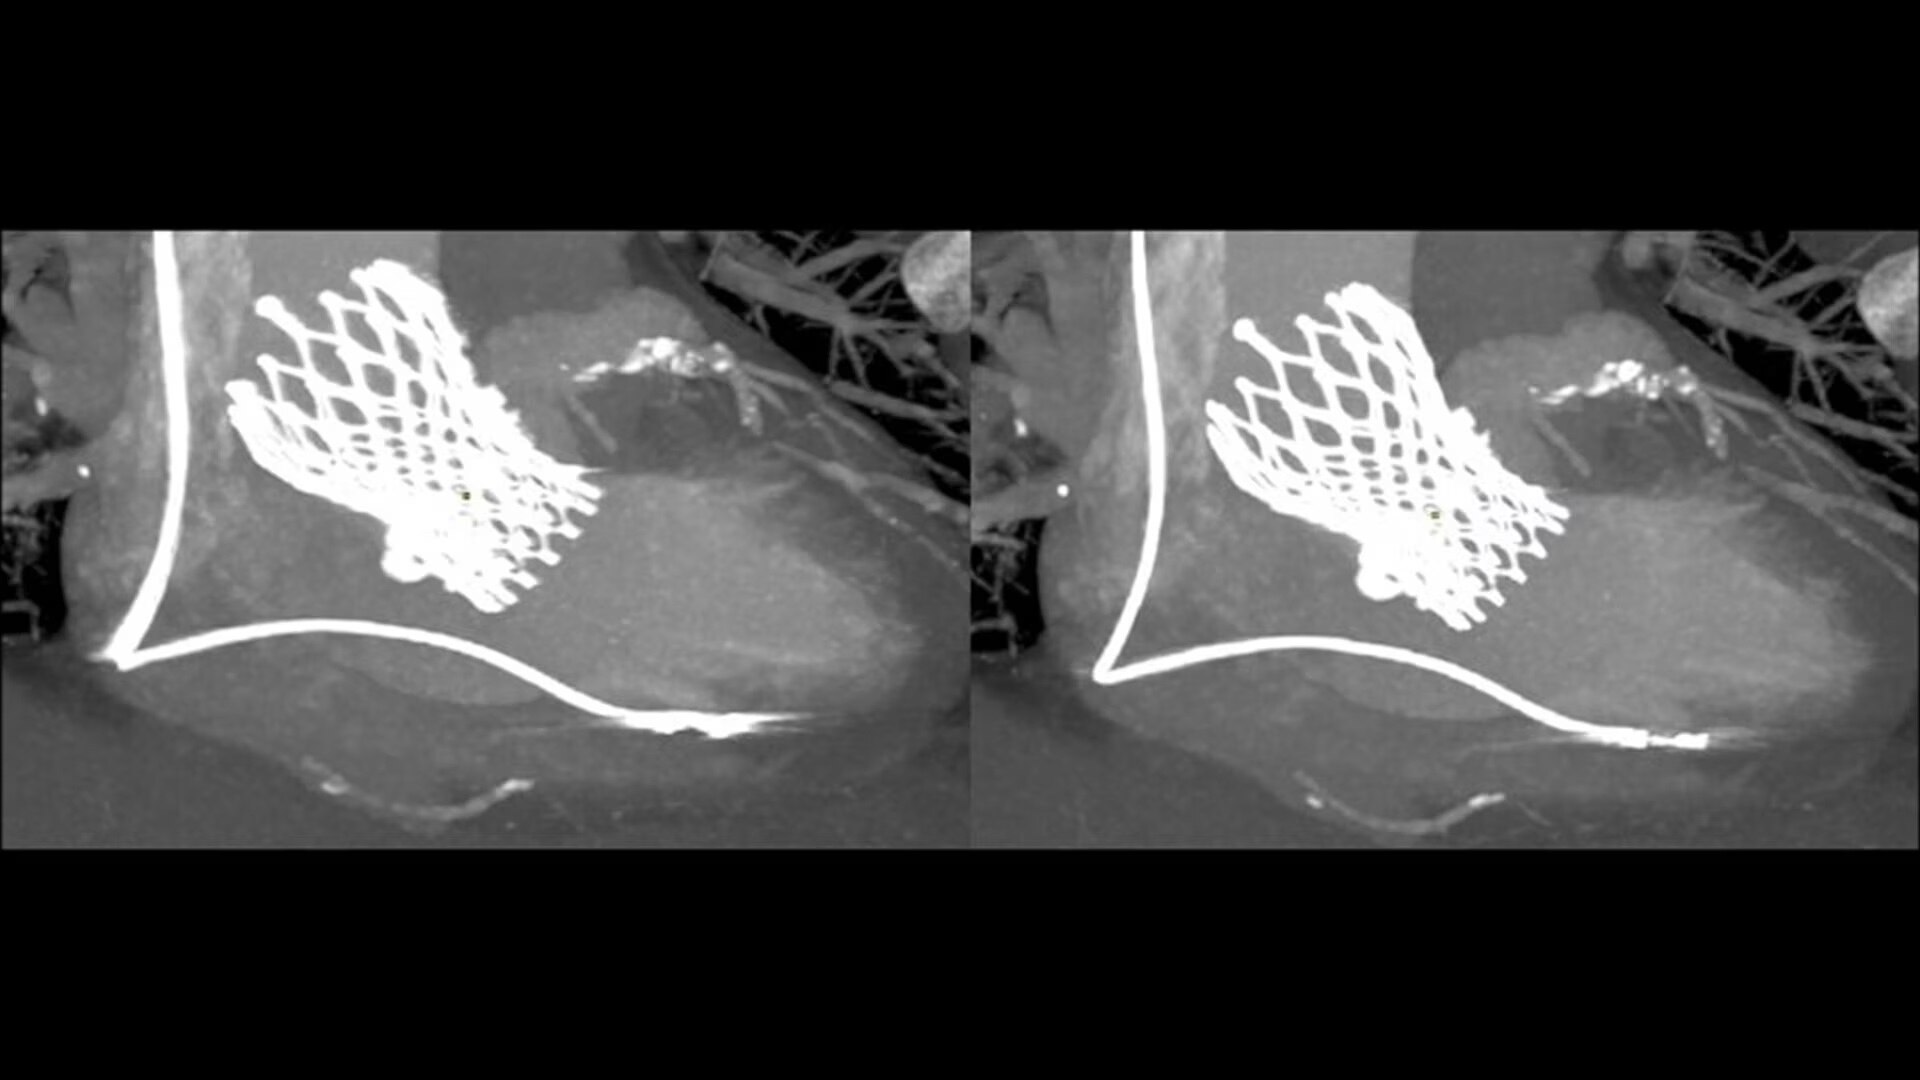

SnapShot Freeze 2

Intelligent and automated whole-heart motion correction for enhanced Cardiac CT imaging.

Motion correction

6x reduction in motion artifacts1

Temporal resolution

19.5 msec effective temporal resolution at 0.23s/rotation gantry speed2

Automated

Whole-heart motion correction